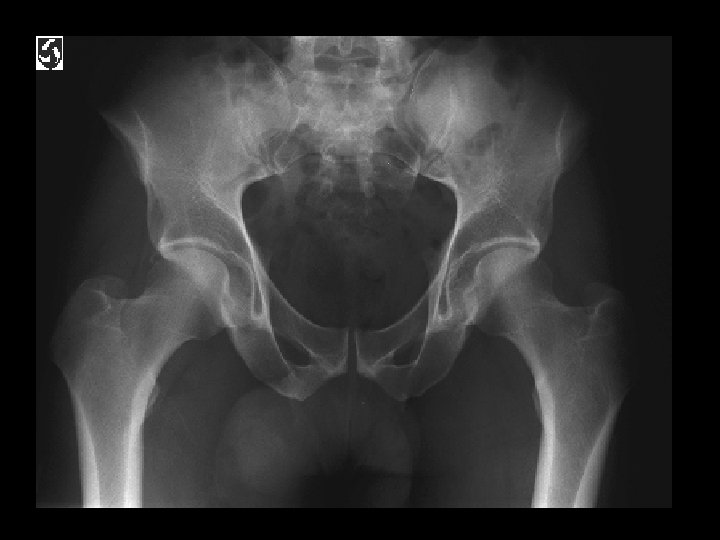

Ankylosing Spondylitis • Findings: – fused SI joints – right hip erosions – lumbar syndesmophytes • Sero-negative chronic inflammatory disease • Starts in the low back and progesses upward • ddx (sacroilitis) – bilateral • ank spond • IBD – unilateral • Reiter’s • psoriasis